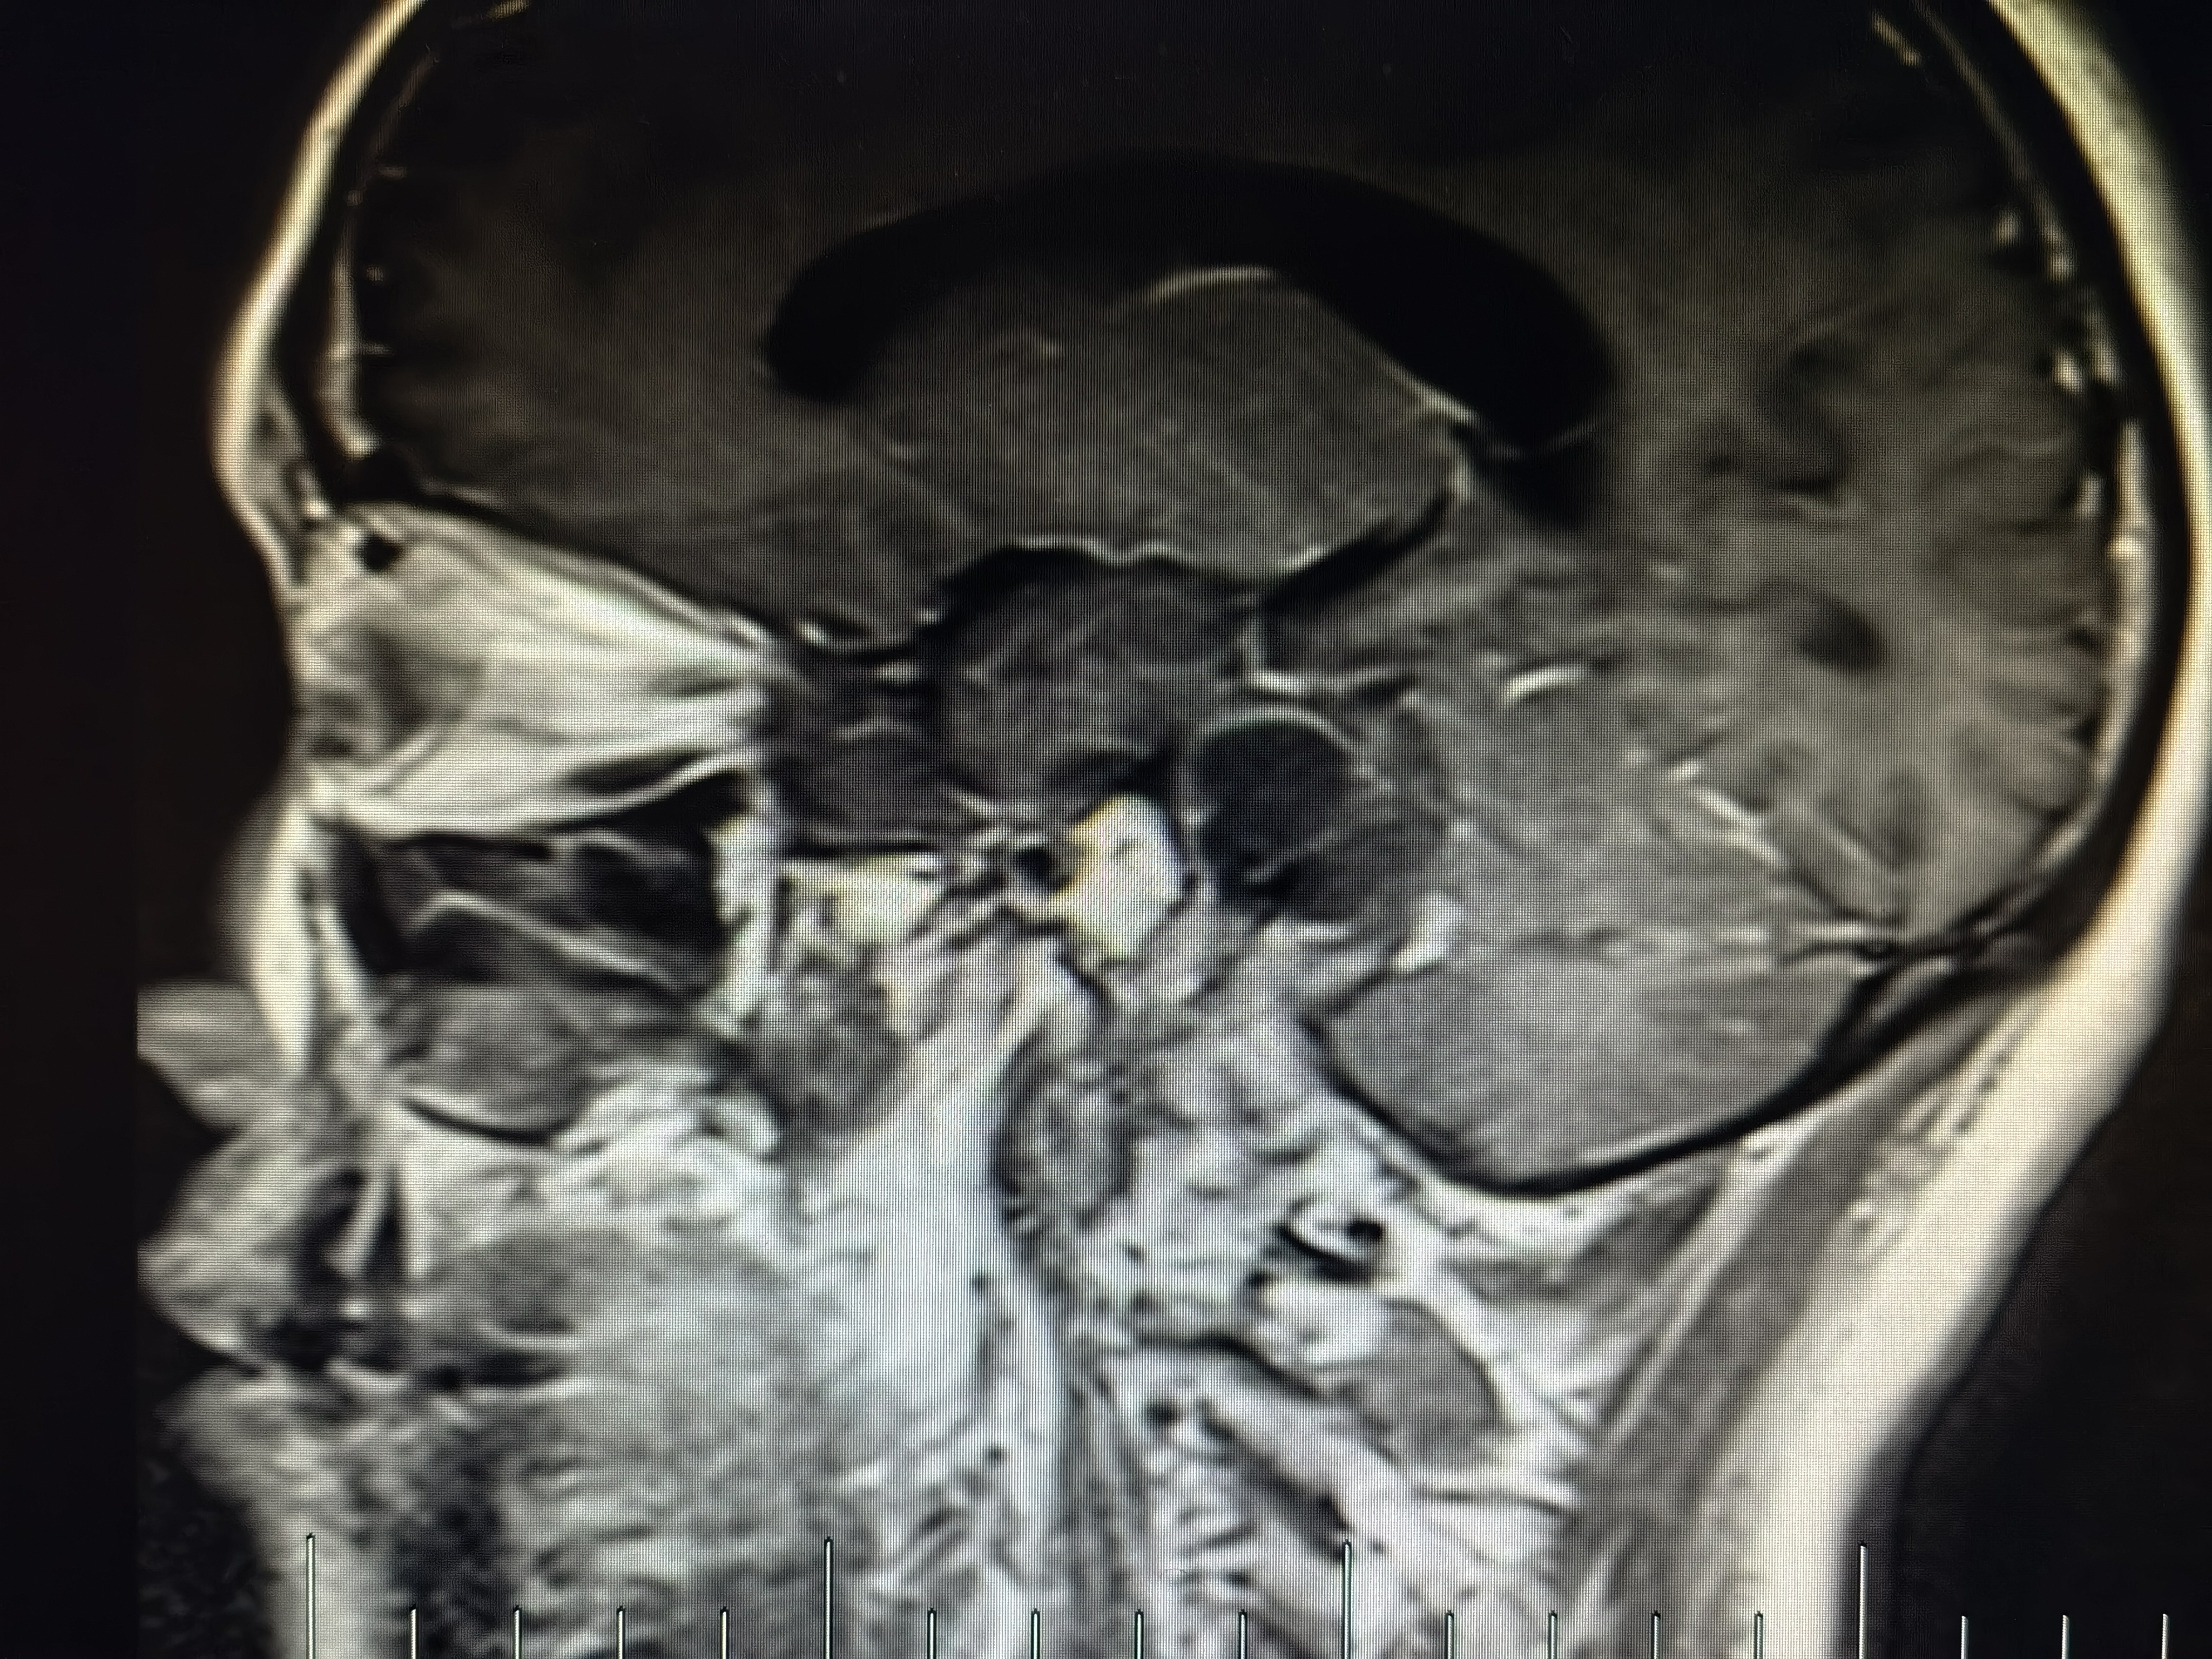

术前磁共振